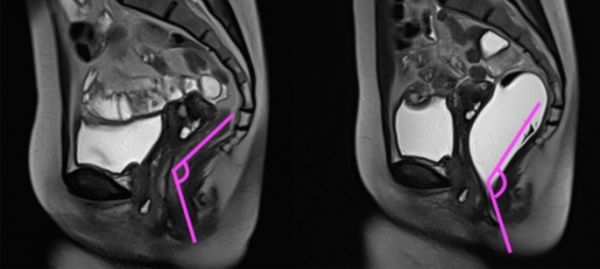

由于便秘存在多种类型,一般需要针对性采用不同检查方法进行鉴别和诊断。排粪造影,指的是使用 钡糊(一种影像学对比剂)直肠内注射模拟粪便,并通过影像 学观察 和分析患者整个排便的过程,从而评估排便相关盆底肌、直肠肛门及周围组织等排便活动中不同时间段的功能和重要解剖学参数变化的一种检查方法。磁共振排粪造影的优点是该检查可以进行实时动态的观察记录并且没有辐射,推荐用于怀疑为排便功能障碍型便秘患者的辅助检查,特别适用于存在形态和解剖学改变的便秘。排粪造影检查常常联合结肠传输实验、直肠肛门测压、球囊逼出实验等方法,用于慢性便秘的准确分类和分度,以便临床医生更为全面的掌握病情,制定更为合理的治疗方案。

排粪造影